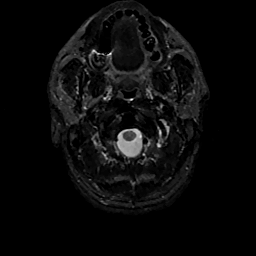

MR Study #11, May 5, 1991 -- Slice #0

[Home][Help][Clinical][Tour 1][Tour 2] Slice 0